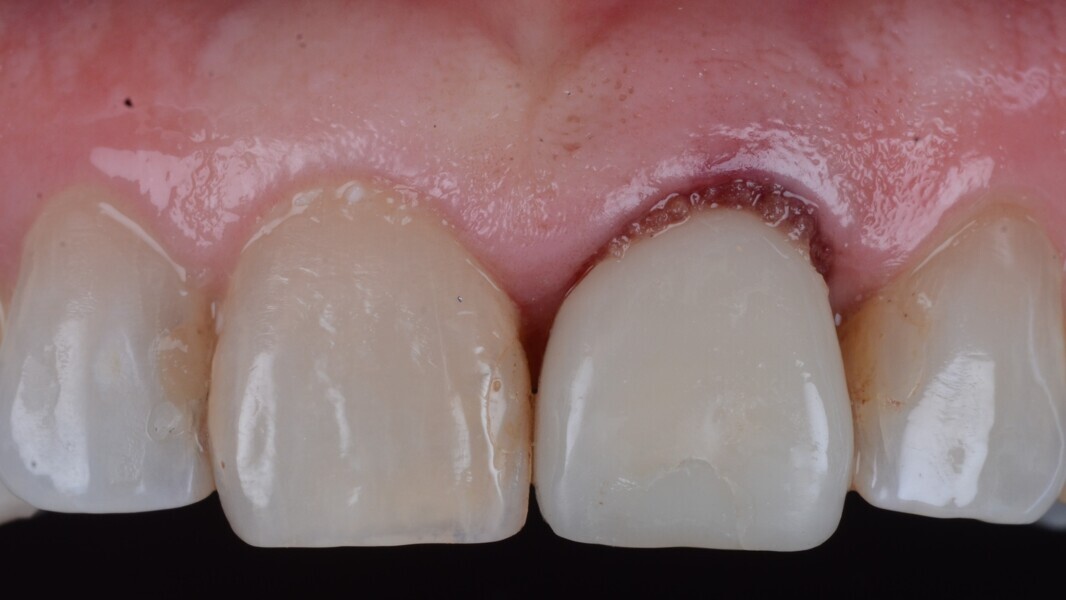

Fig. 32: Final result close up.